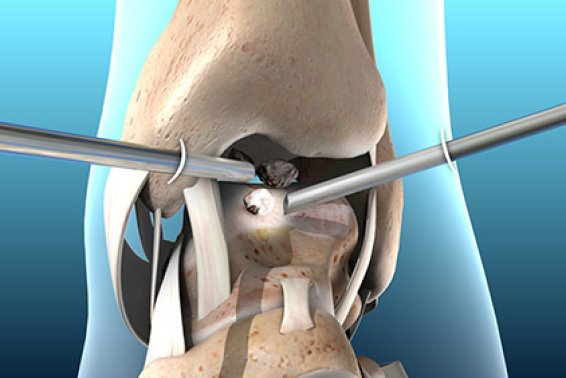

What is keyhole surgery? And what are its benefits?

Keyhole surgery, a term used colloquially to describe minimally invasive procedures, has become a game-changer in the realm of foot and ...